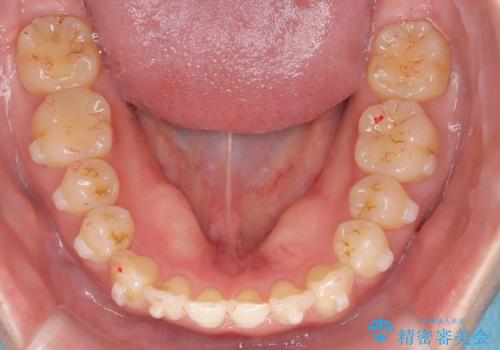

下顎前歯の叢生がとれ右上2の反対咬合も改善し患者様にも満足していただけました。治療期間は1年~1年半を見込んでいましたが、患者様の協力もあり10か月で矯正を終えることが出来ました。